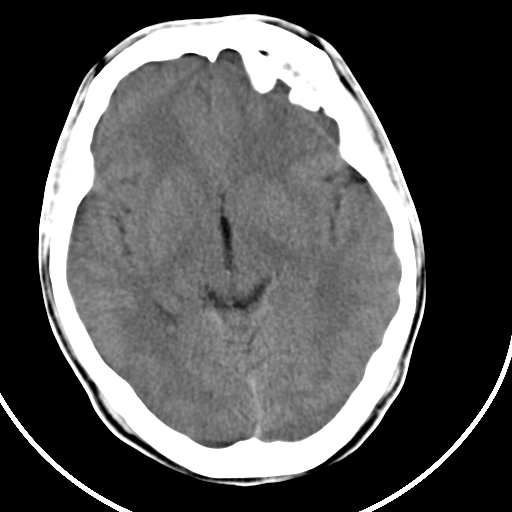

标题: CT21939:男20岁,外伤一年后,现头疼. [打印本页]

标题: CT21939:男20岁,外伤一年后,现头疼.

颅骨凹陷性骨折并压迫脑组织致大脑镰下疝!

硬膜外血肿机化

如果是骨折,外板正常内板这么明显凹陷,请问这样的骨折是怎样形成的?形成的机理是什么?有没有可能形成?

硬膜外血肿伴包膜钙化

考虑硬外血肿并血肿肌化? 难道是传说中的盔甲脑?

左侧额部硬膜外血肿机化、骨化。

左侧额部硬膜外血肿机化、骨化